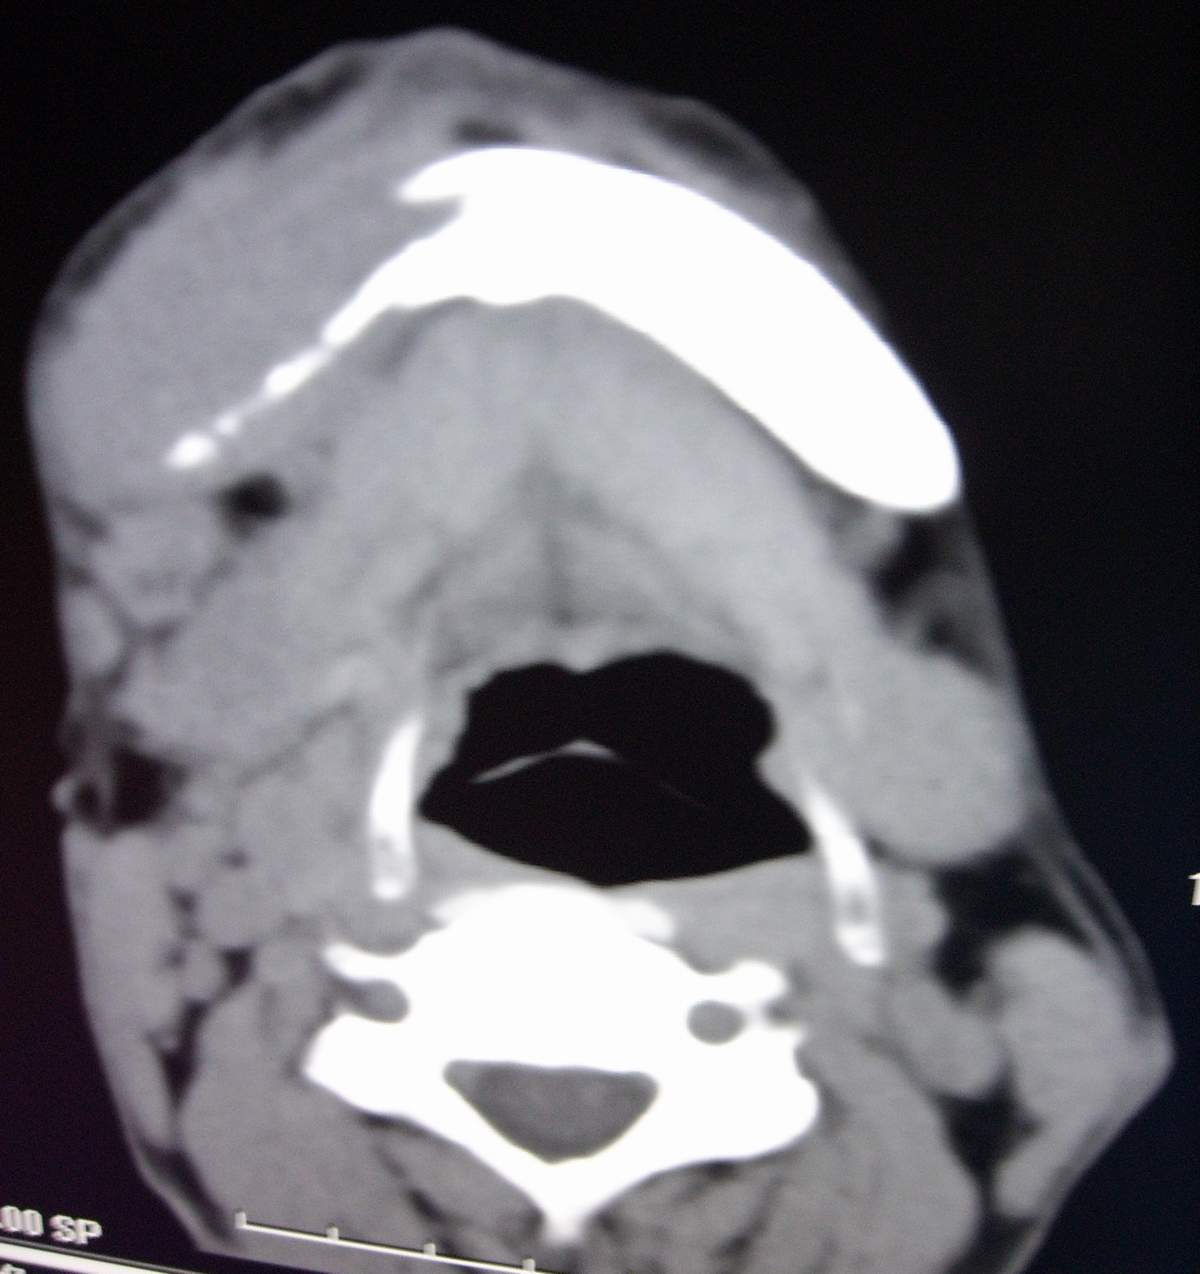

男,54岁,右下颌肿痛1月余。

右侧下颌骨水平部及升支呈溶骨性破坏,无明显膨胀,周围见软组织肿块。

右下颌骨溶骨性破坏,代之以团块状软组织影,内有斑片状瘤骨,边缘骨质有少量骨膜反应,考虑:右下颌骨骨肉瘤。期待病理。